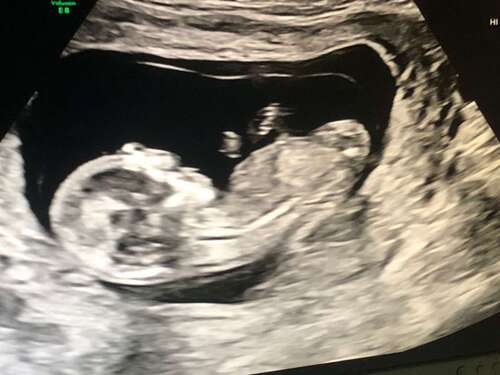

Wat denken jullie 馃檲

Ik denk een meisje

Heb je meer foto鈥檚?

Dit zijn de foto's die ik heb, ik ben benieuwd heb er zelf totaal geen verstand van 馃グ

Door de andere foto neig ik meer naar een meisje 馃┓ maar kan het helaas niet goed zien